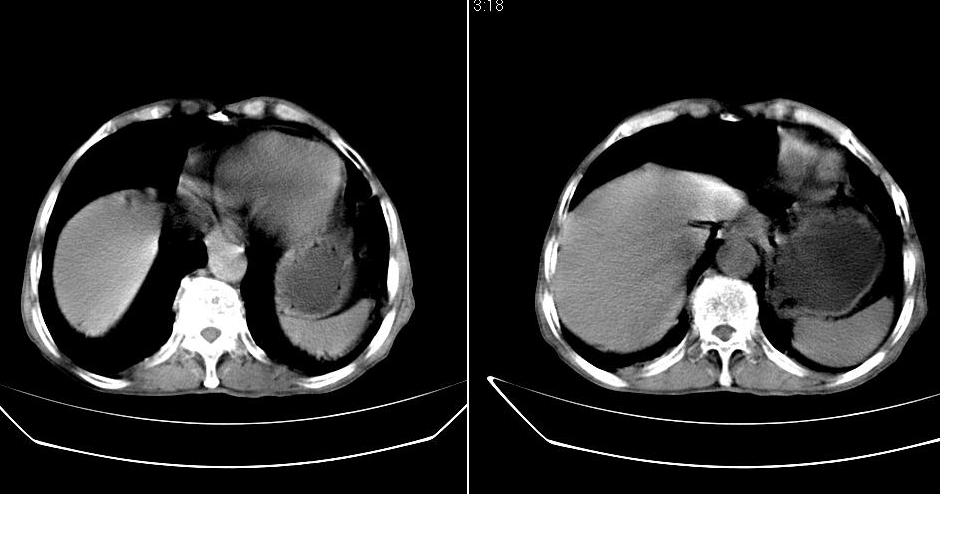

男,76岁,上腹部疼二天来就诊,彩超提示肝左叶占位,随后做上腹部ct平扫,今天做上腹部ct增强扫描,手工推药,效果不好,请谅解。

肝左叶s4肿块强化形式大概是:慢进慢出,逐渐强化----考虑血管瘤/腺瘤?{动脉期应更提前扫}。

肝内胆管积气扩张,胆囊增大,肝右前叶低密度灶,逐渐强化,一元论,胆系感染,局限性肝脓肿;右肾囊肿。

考虑肝s4段肝脓肿可能?未排除肝癌。右肾上极囊肿。